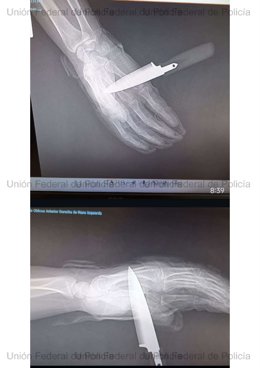

Radiografía de la mano del agente de la Policía Nacional apuñalado en Baza (Granada)

Radiografía de la mano del agente de la Policía Nacional apuñalado en Baza (Granada) - UNIÓN FEDERAL DE POLICÍA (UFP)

Acto seguido, el atacante intentó asestar una segunda puñalada que el policía logró repeler parcialmente, aunque el arma blanca llegó a atravesarle la mano.

No obstante, el agente hizo uso de su extensible reglamentaria y con la colaboración de su compañera consiguió reducir y detener al agresor, que fue trasladado a dependencias policiales para su ingreso en calabozos. Por su parte, el agente herido tuvo que acudir a un centro hospitalario con el cuchillo aún clavado.